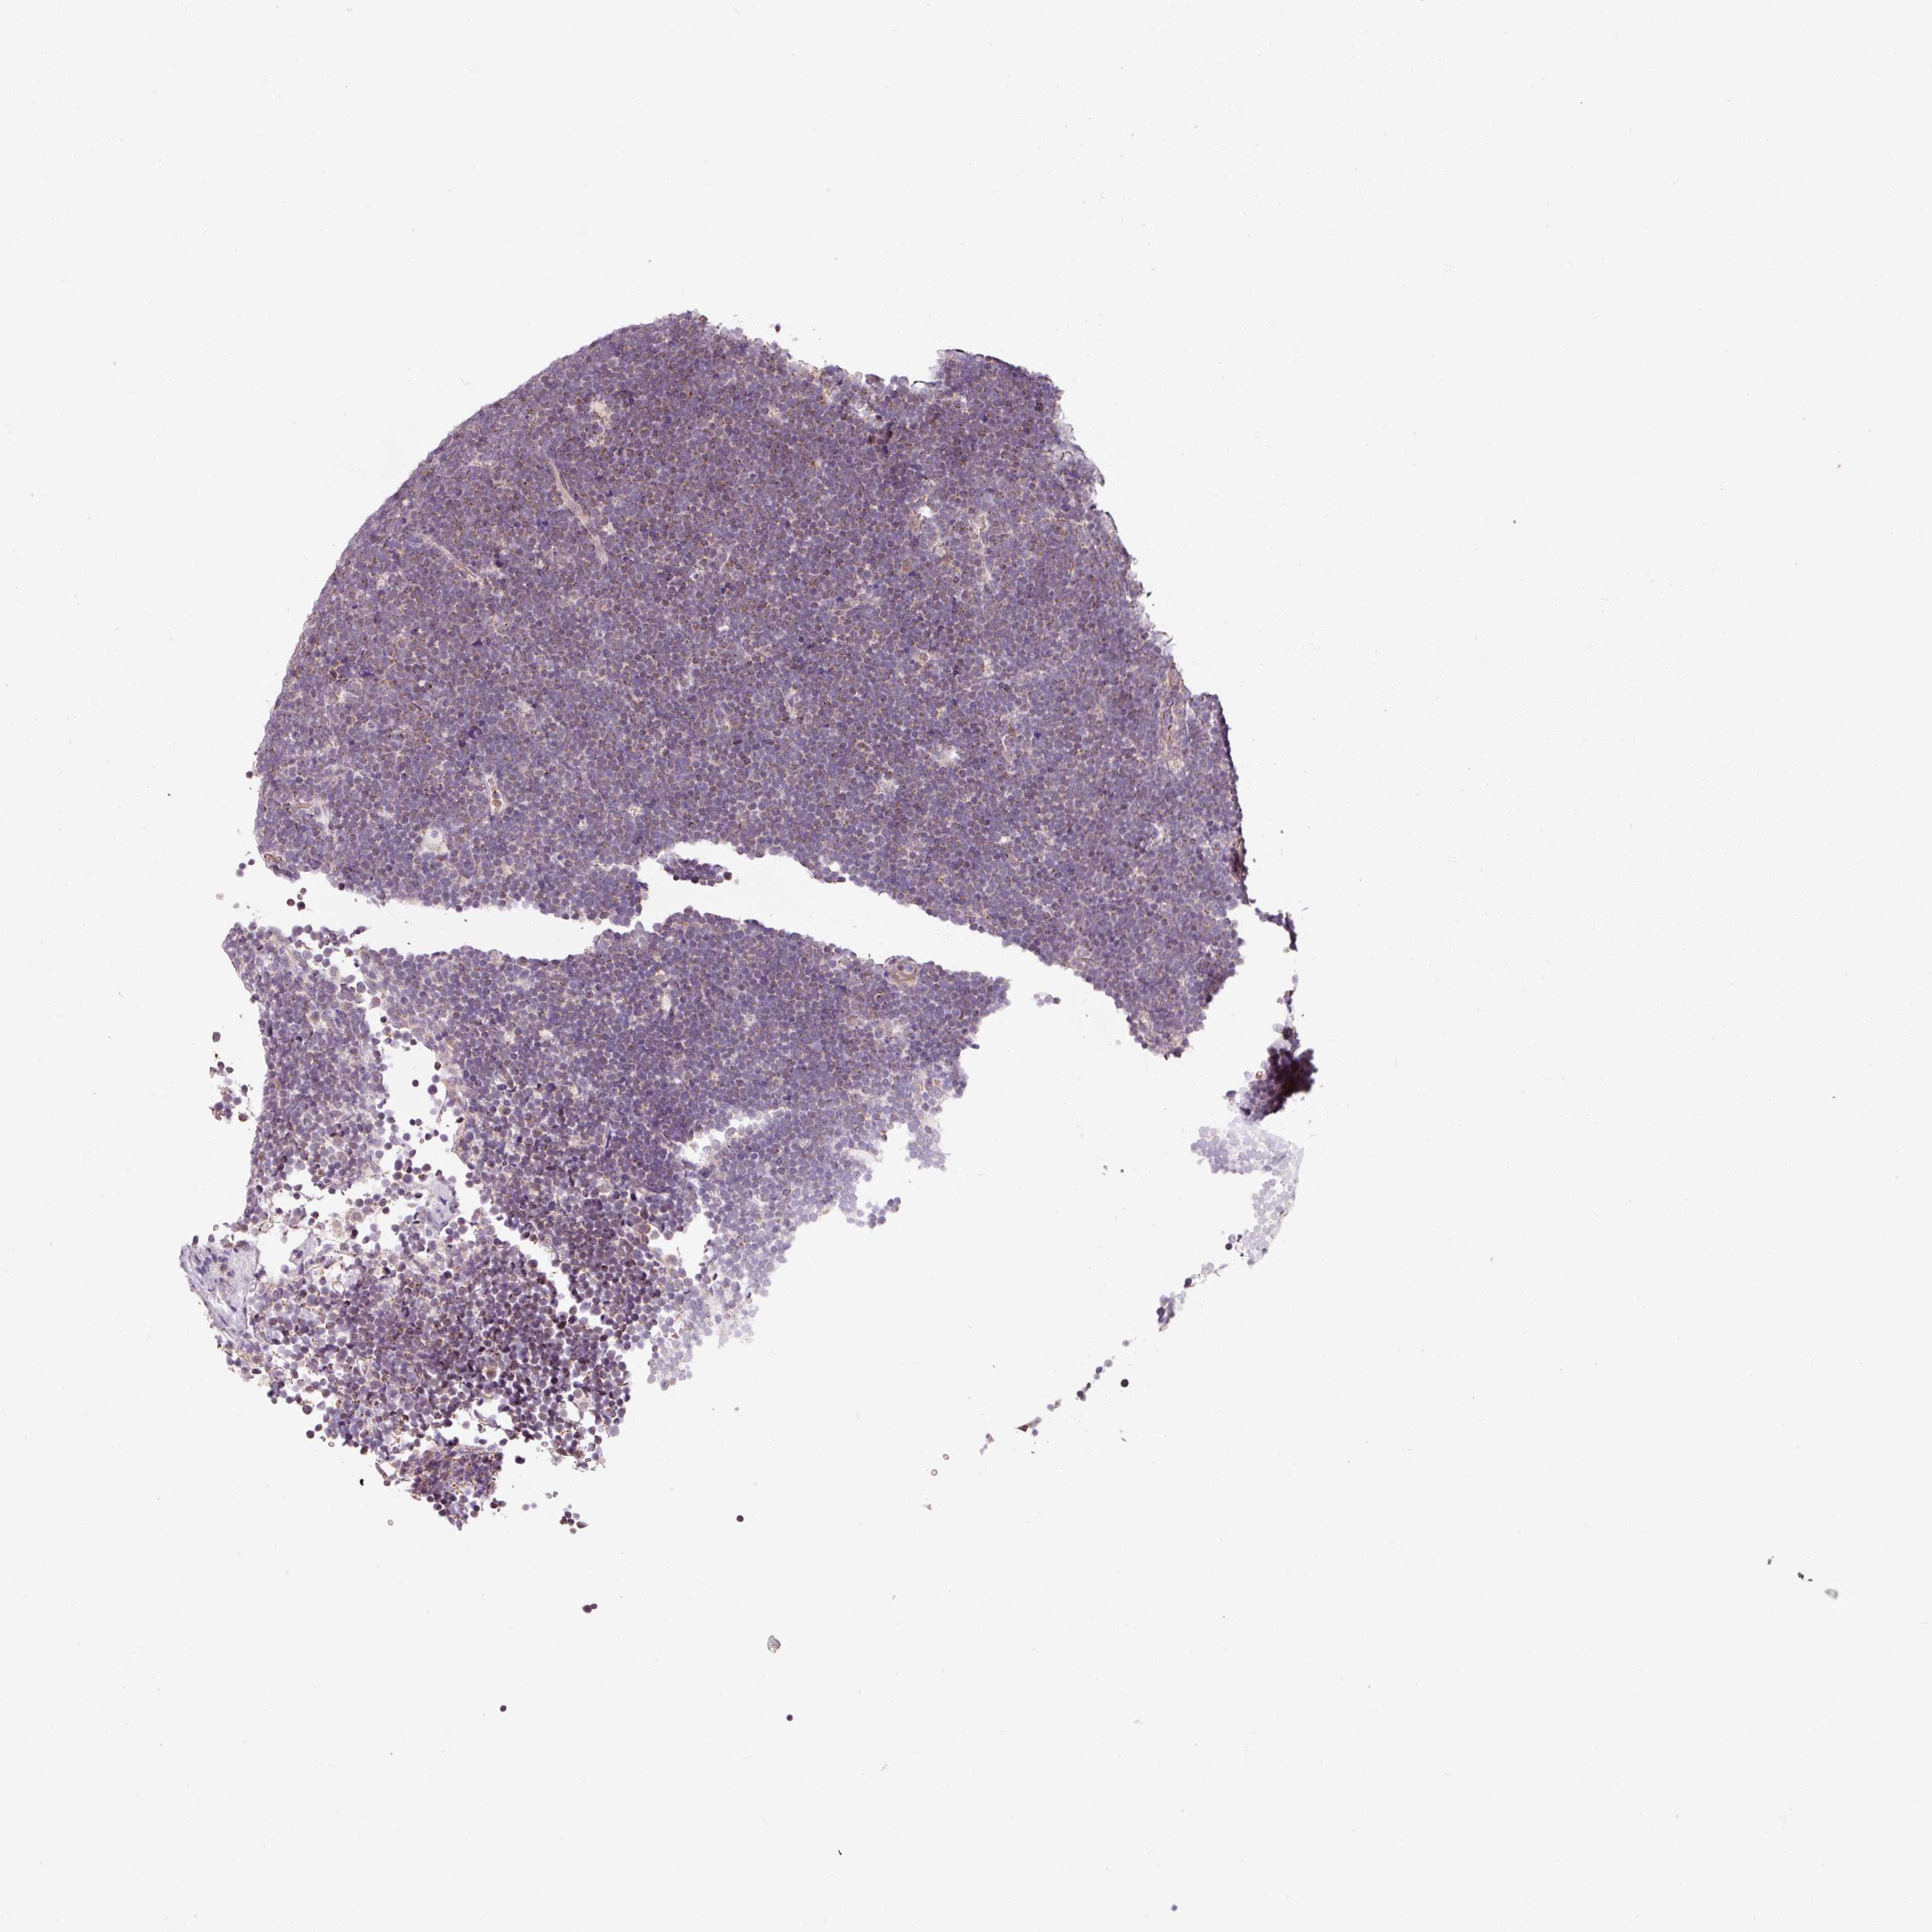

CANCER LYMPHOMA Show tissue menu

LYMPHOMA - Protein expressioni

A mouse-over function shows sample information and annotation data. Click on an image to view it in a full screen mode. Samples can be filtered based on level of antibody staining by selecting one or several of the following categories: high, medium, low and not detected. The assay and annotation is described here.

Each image is clickable and will lead to virtual microscopy that enables deeper exploration of all samples and also displays staining intensity scores, fraction scores and subcellular localization as well as patient and tissue information for each sample.

Antibody HPA053004

Staining

High

Medium

Low

Not detected

Intensity

Strong

Moderate

Weak

Negative

Quantity

>75%

75%-25%

<25%

None

Location

Nuclear

Cytoplasmic/membranous

Cytoplasmic/membranous,nuclear

Hodgkin's disease, NOS

Malignant lymphoma, non-Hodgkin's type, High grade

Malignant lymphoma, non-Hodgkin's type, Low grade